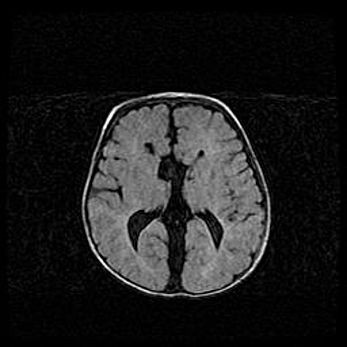

Сообщающаяся гидроцефалия. Кистозная энцефаломаляция головного мозга.

Возраст: 3 месяца 4 дня

Вес: 3100 г

Пол: женский

Окружность головы: 34 см

Срок гестации: 31 неделя

Кистозная энцефаломаляция головного мозга - одна из форм поражения головного мозга в детском возрасте. Характеризуется возникновением множественных и распространённых кист в коре, белом веществе и подкорковых образованиях головного мозга у плодов, новорождённых и детей раннего возраста. Развитие кистозной энцефаломаляции связано с внутриутробной асфиксией и гипотонией, родовой травмой, тромбозом синусов, пороками развития сосудов, инфекциями, сепсисом и другими причинами. Наиболее значимые инфекционные агенты: вирусы простого герпеса, цитомегалии, краснухи, токсоплазмы, энтеробактерии, золотистый стафилококк и другие.